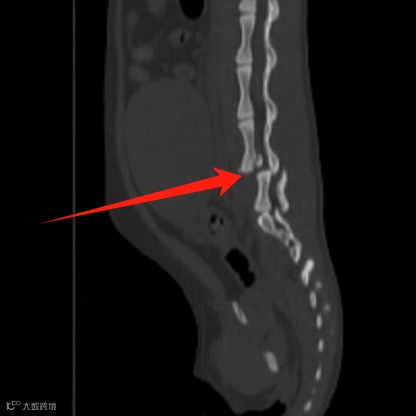

L6-7椎体错位,L7椎体相对于L6背移位,L6椎体连续性丧失,骨碎片掉入L6背侧椎管内,压迫马尾神经。